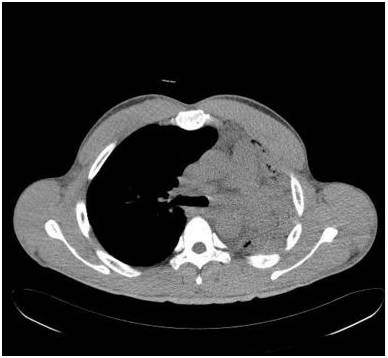

胸部前后位示弥漫不均匀的异常密度影,左肺体积缩小,左肺门区肿块样影与心膈角呈钝角。未增强纵隔窗CT示左肺肺不张,左主支气管完全受阻。增强CT示左主支气管及其段支气管内非强化的肿块。最小密度投影示左肺叶远端支气管重度狭窄,左主支气管及以下层面受阻。